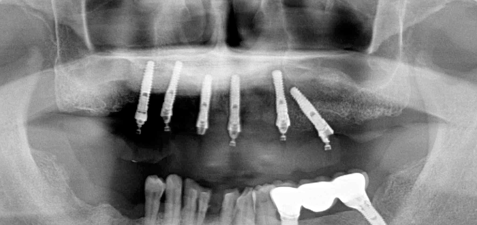

術直後の写真です

オールオン6本のインプラントをいれました

初期固定もよかったので即時荷重をおこなっています

術後2週間 傷もきれいに治ってきています